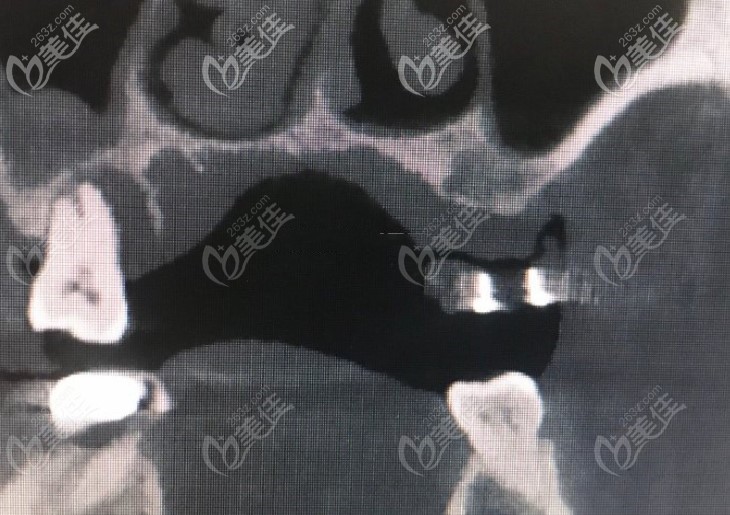

我的CT,显示牙槽骨因为萎缩骨量不足↓↓↓